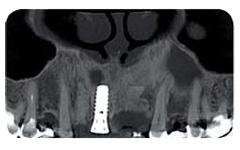

L’obiettivo dell’analisi è quello di valutare lo stato della bocca prima di eseguire un qualsiasi trattamento odontoiatrico, andando a evidenziare eventuali lesioni ossee, infiammatorie o cistiche; analizzare lo stato di salute della dentizione, soprattutto nelle fasi di sviluppo; tenere sotto controllo eventuali malformazioni o constatare la presenza di neoplasie mascellari o mandibolari.

Lo studio si avvale di specifiche strumentazioni per assicurarti un’accurata analisi ortodontica. In primis, lo staff medico si affida all’alta tecnologia del sistema Cone Beam NewTon 5G XLUno, fondamentale per settori medici quali implantologia, endodonzia, chirurgia orale e ortodonzia, in grado di creare immagini 3D capaci di mostrare patologie potenziali e anomalie strutturali con una precisione senza precedenti; dall’altra si sottolinea la presenza della tecnologia SafeBeam™, il sistema più sicuro sia per i pazienti che per lo staff medico. Grazie a questo strumento, gli esperti eliminano qualsiasi possibilità di esposizioni radioattive, mantenendo un contrasto dell’immagine nitido e definito, a prescindere dalle dimensioni anatomiche o dalla densità ossea osservata.